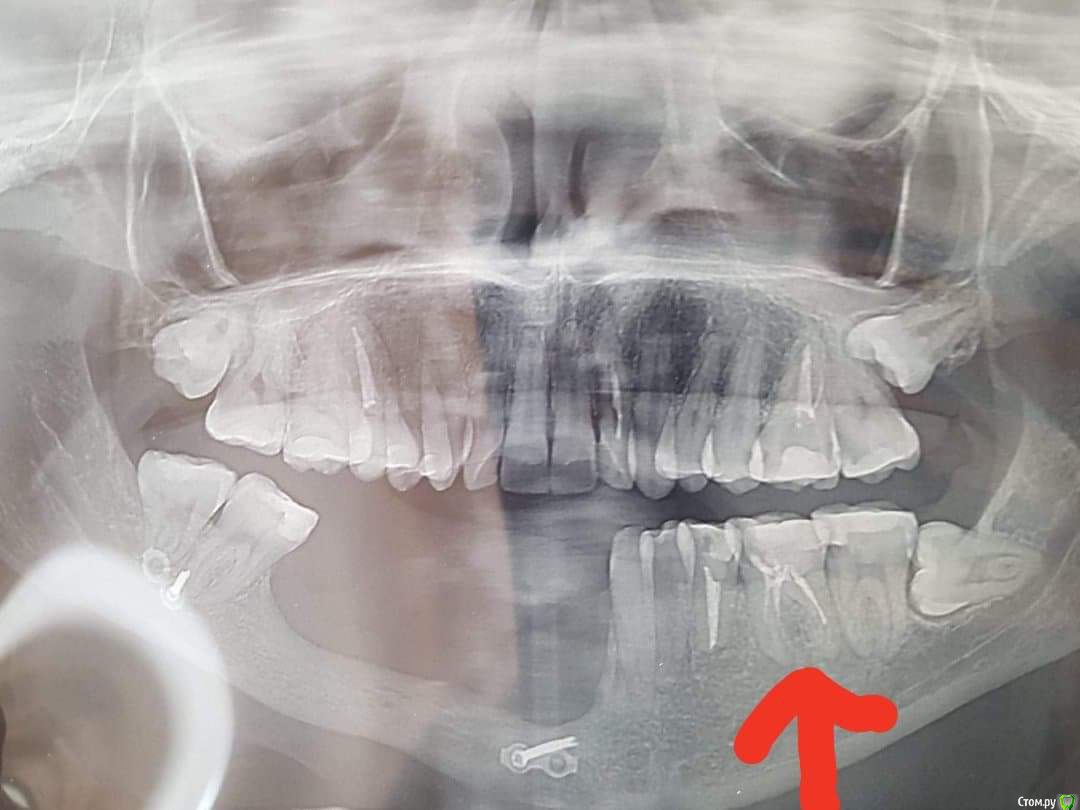

martynyukm Опубликовано 6 августа, 2018 Поделиться Опубликовано 6 августа, 2018 (изменено) Здраствуйте,один врач (хирург)сказал вырвать зуб,обьяснив,что он уже мертв и его не спасти. Боль иногда бывает,но на данный момент нет. Другой врач стоматолог сказал,что вырвать всегда успеешь,что лучше подождать. Хирург обьяснил по снимку,что под ним черные точки и как-то он может повлиять на соседний зуб,на котором у меня держится протез. Посоветуйте,пожалуйста,рвать или нет. Изменено 6 августа, 2018 пользователем martynyukm Ссылка на комментарий

martynyukm Опубликовано 6 августа, 2018 Автор Поделиться Опубликовано 6 августа, 2018 Вот еще снимок Ссылка на комментарий

red_butler Опубликовано 6 августа, 2018 Поделиться Опубликовано 6 августа, 2018 перелечить и протезировать Ссылка на комментарий

Бендер Опубликовано 6 августа, 2018 Поделиться Опубликовано 6 августа, 2018 Выглядит вполне лечибельно. Перелом давно был? Ссылка на комментарий

martynyukm Опубликовано 7 августа, 2018 Автор Поделиться Опубликовано 7 августа, 2018 Это была то ли кластобласт то ли бластокласт челюсти и послед. Пересадки кости для наращивания челюсти. Последняя операция была 5 лет назад Ссылка на комментарий